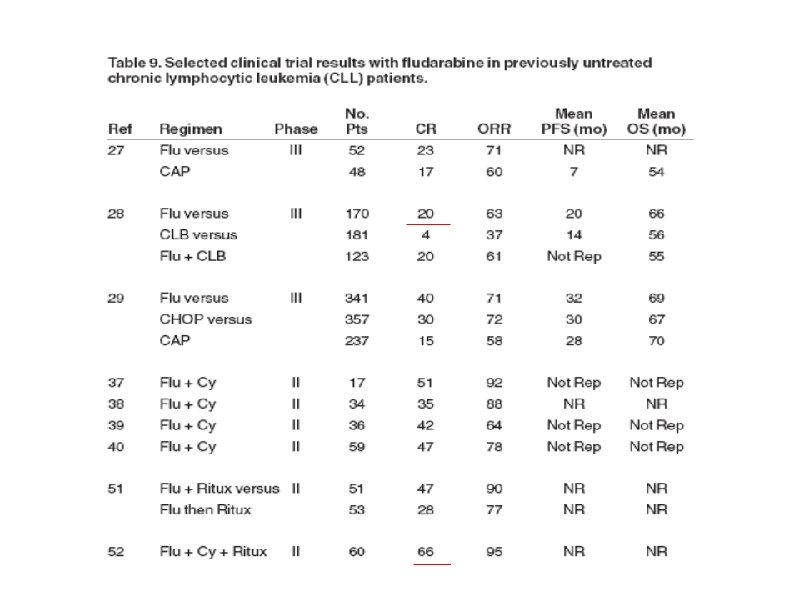

Тактика лечения больных ХЛЛ на постремиссионном этапе